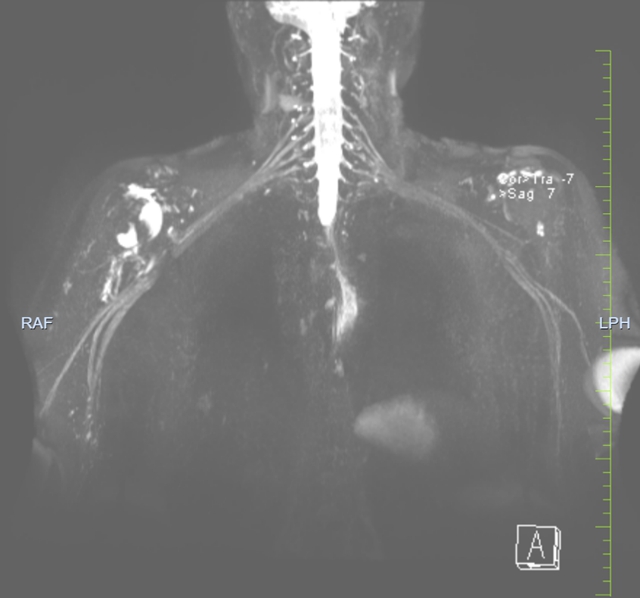

经过详细检查,骨科副主任、运动促进健康中心主任、骨与关节外科主任李忠教授,刘俊才副教授团队发现陈奶奶的情况比想象中复杂:不仅有肩袖损伤,还合并了臂丛神经损伤。这种"双重损伤"就像电话线(神经)和弹簧(肌腱)同时出了问题,需要“双管齐下”的治疗方案。

手术团队决定采用联合手术方案,由刘俊才副教授主持手术:先像"排雷"一样仔细探查受损神经,解除压迫;再像"缝补衣服"一样修复撕裂的肩袖肌腱。整个手术过程就像在显微镜下做精细的"针线活",需要极高的精准度。